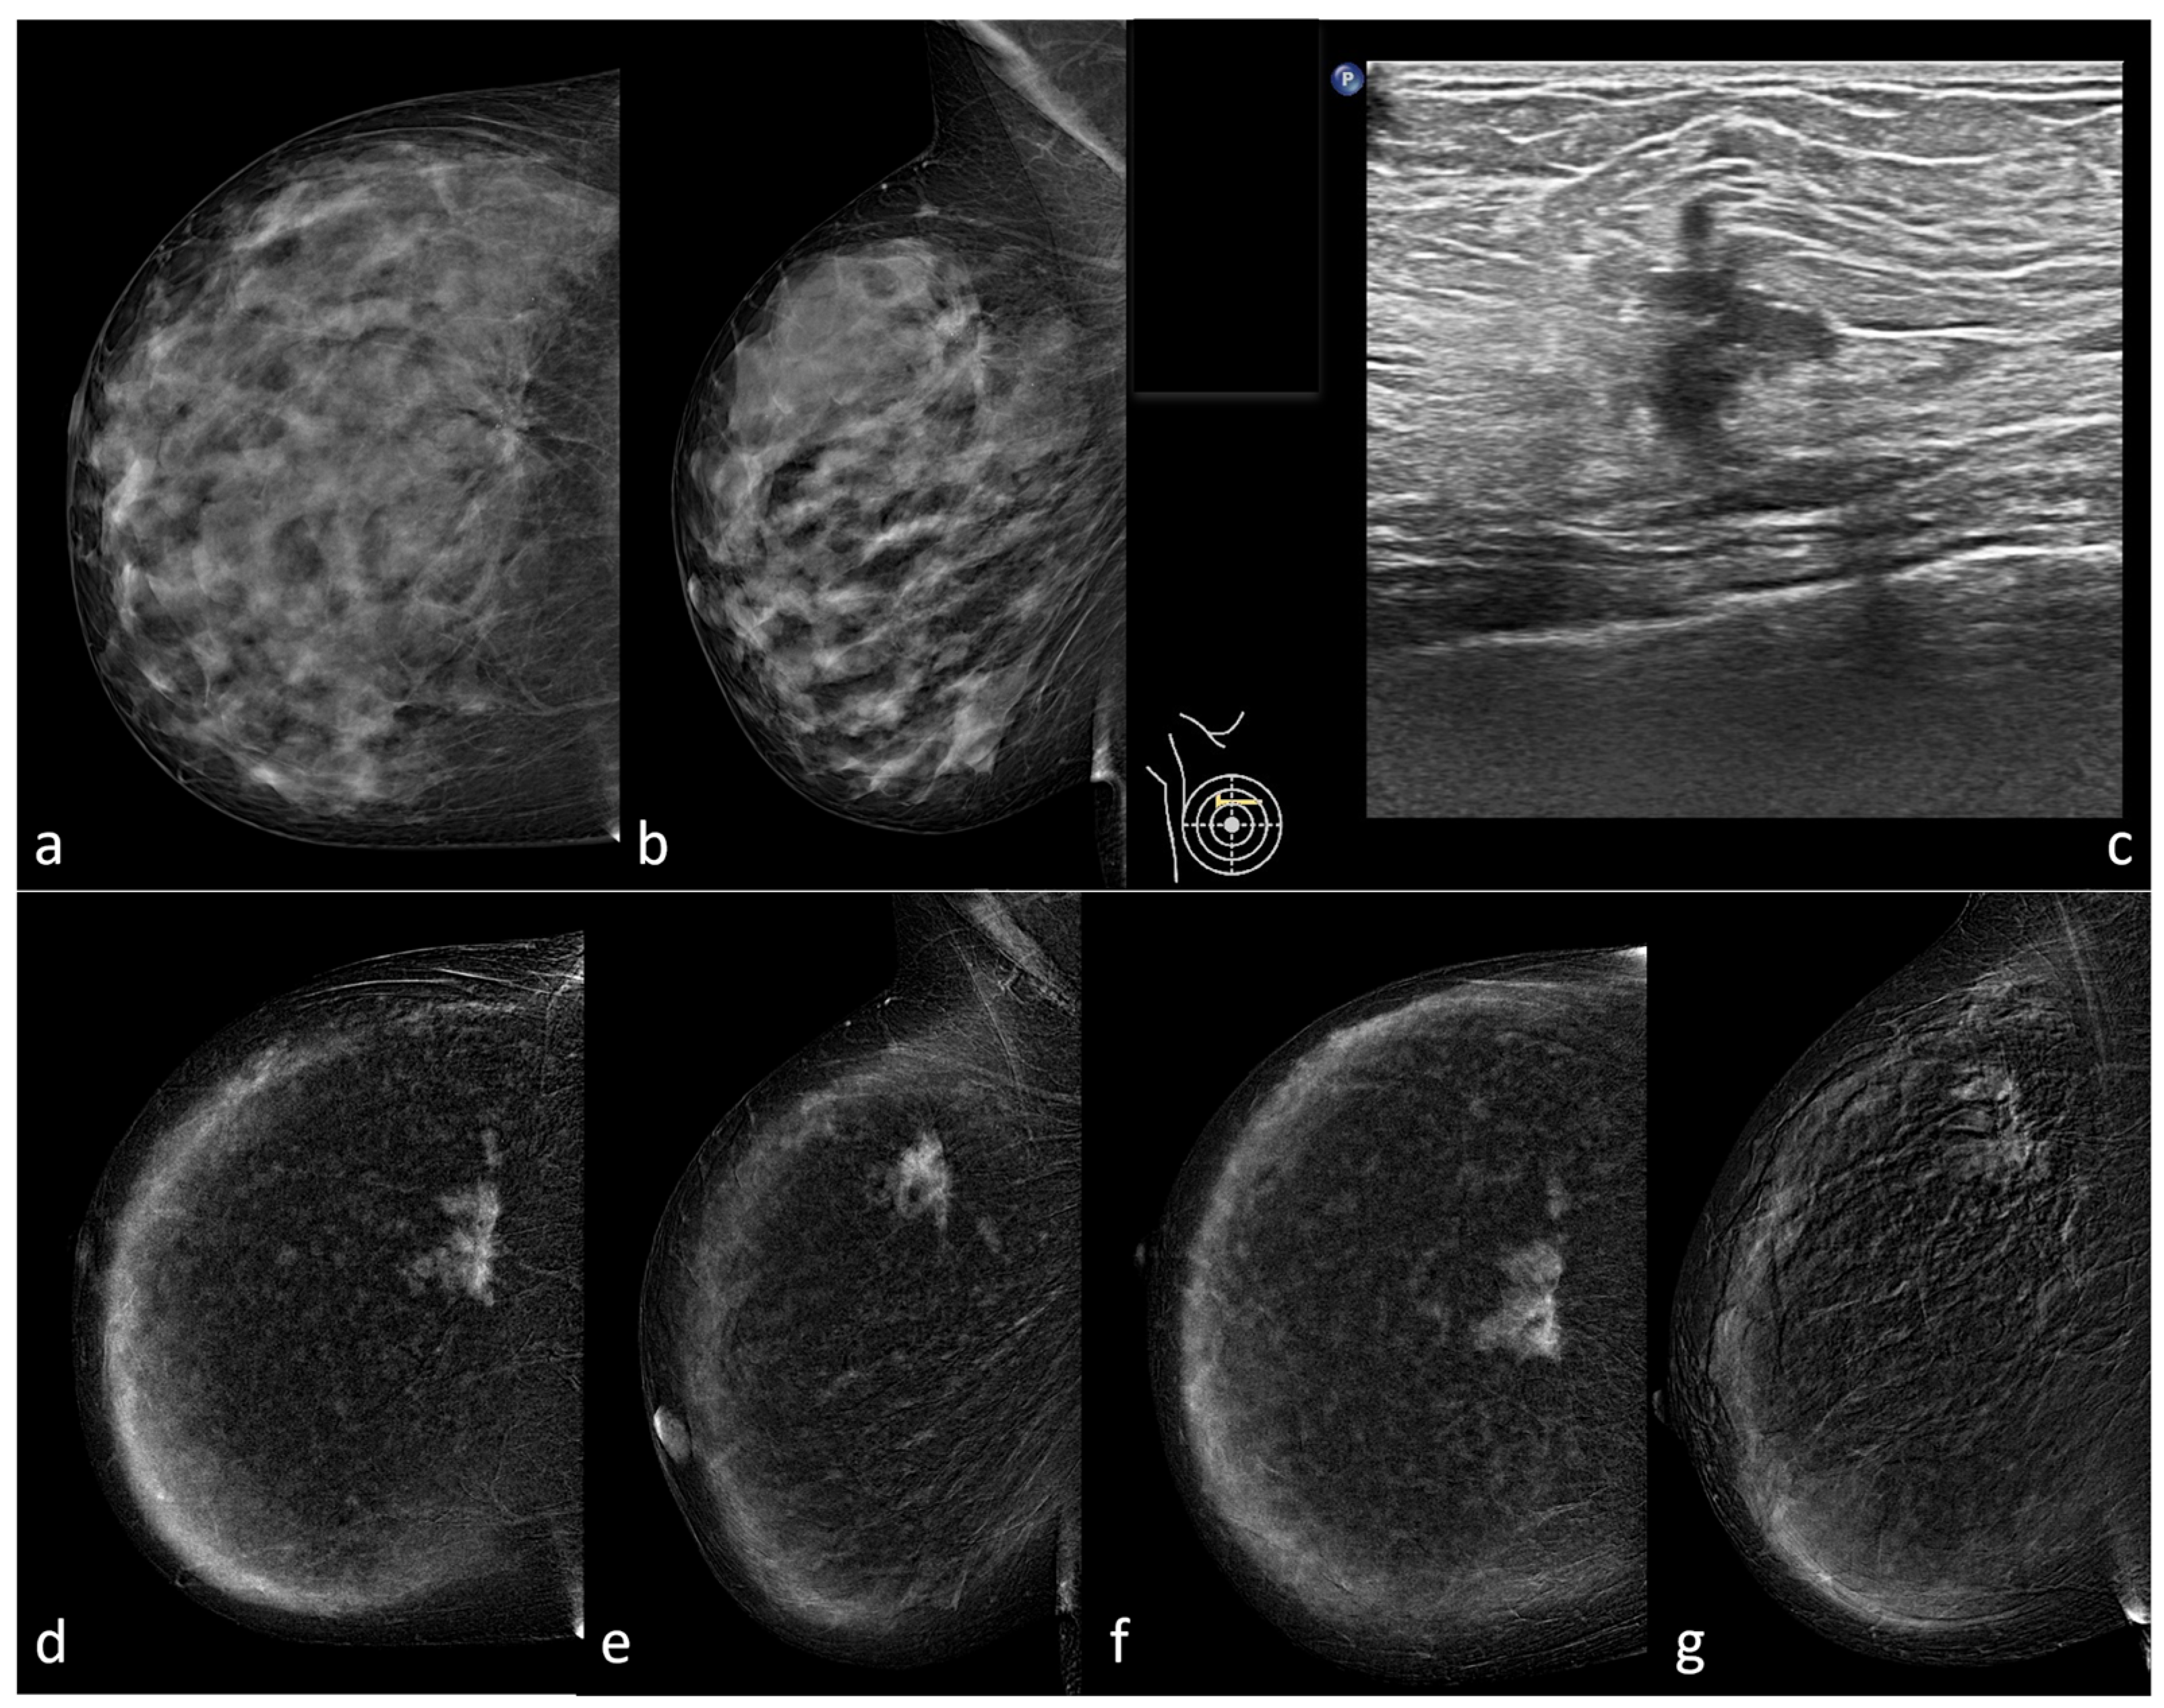

2. Materials and Methods

2.2. Imaging Techniques

2.3. Imaging Evaluation and Interpretation